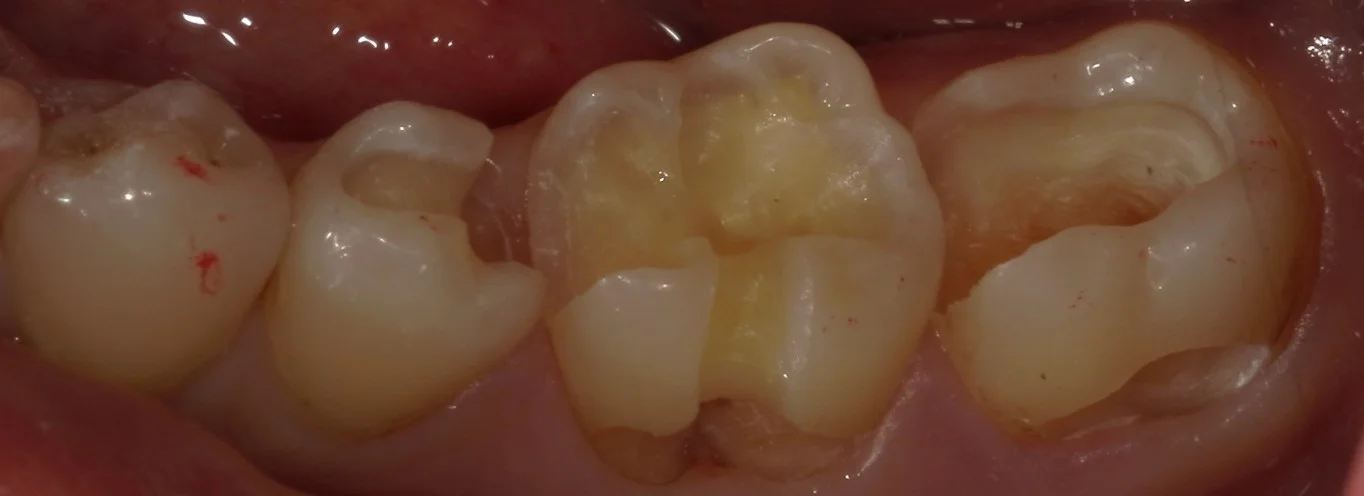

まずは術前ですね。

こちらの金属が入っている3本が治療予定の歯です。

右の2本については金属の下のみならず、根本の歯茎辺りにも虫歯があり、非常に広範囲となっています。

また、真ん中の金属については、金属の周りが咬耗と言って、歯が多く削れている状態になっています。

少量であれば削ったりする必要はないのですが、これほど深く削れている場合は、治療する際に邪魔してくることが多いので、今回は一緒に治療することとしました。

そして金属を外し、虫歯を見やすくしたのがこちらです。

一番右側の歯の内面が真っ黒なのが分かるかと思います。

また、先ほど記載した、歯の根元付近も黒いのが出てきたて虫歯が分かりやすくなりましたね。